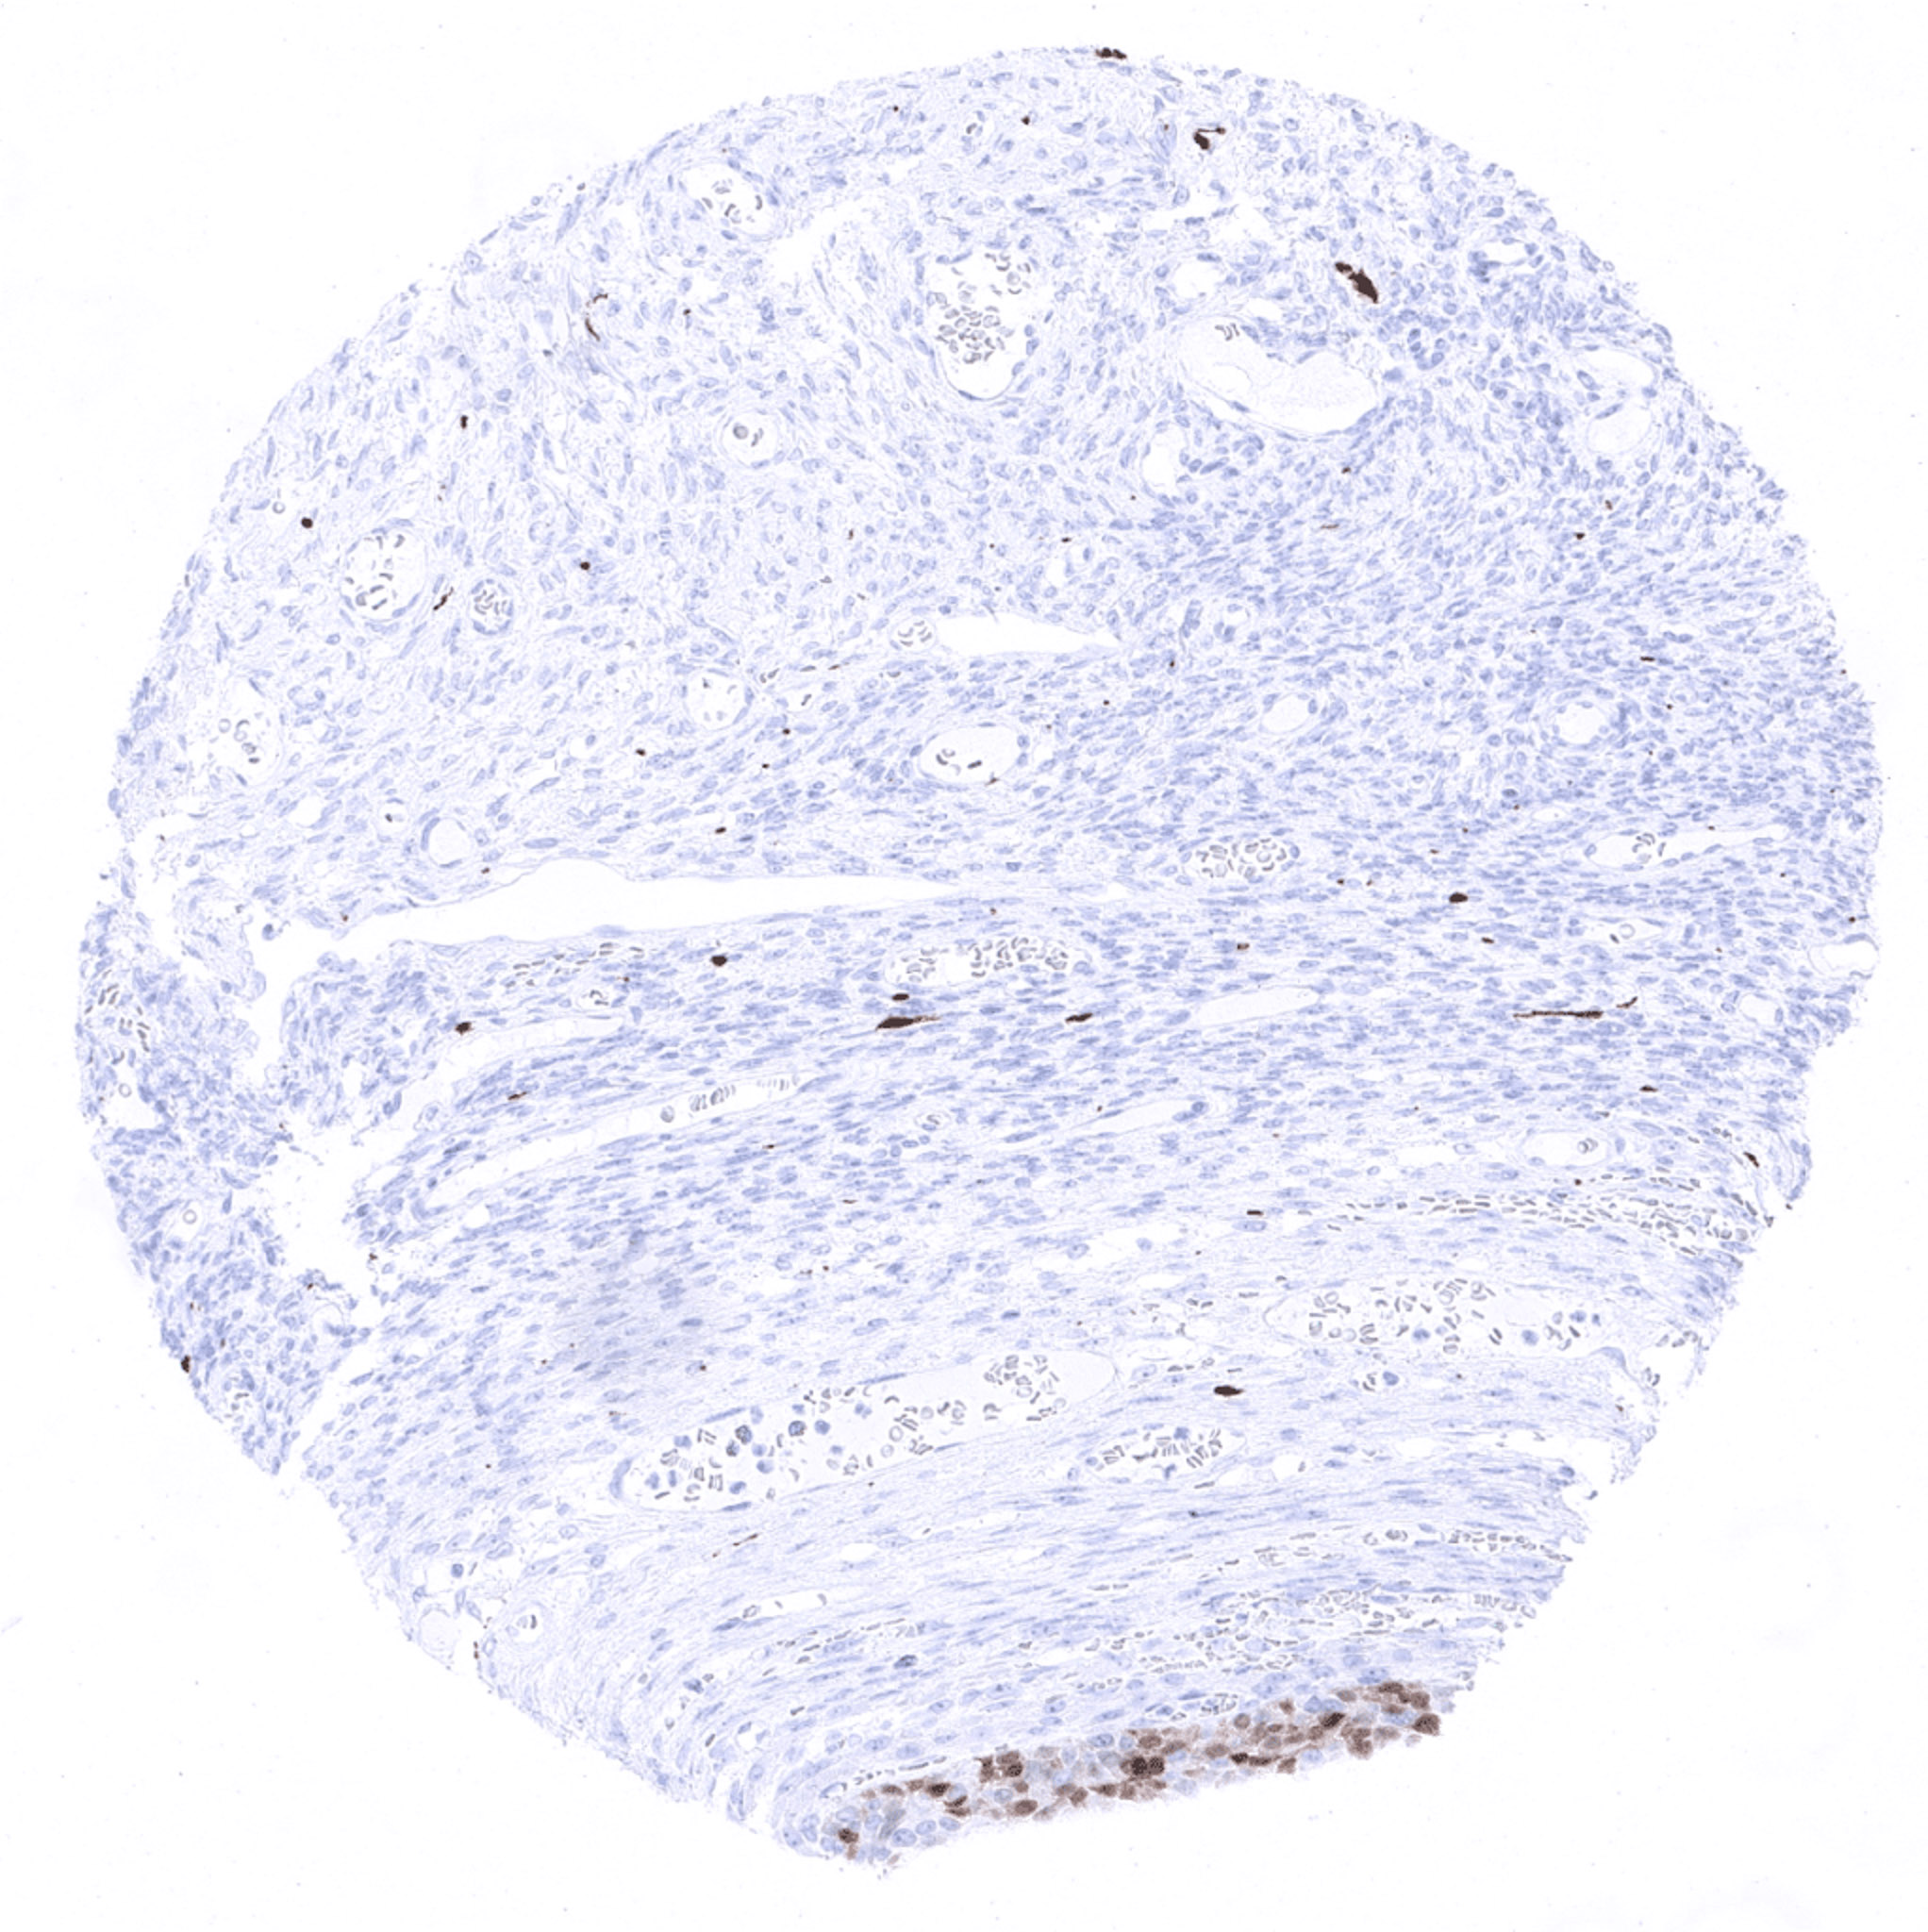

Ectocervix

Endocervix

Skin – Langerhans cells show strong S100 beta positivity.